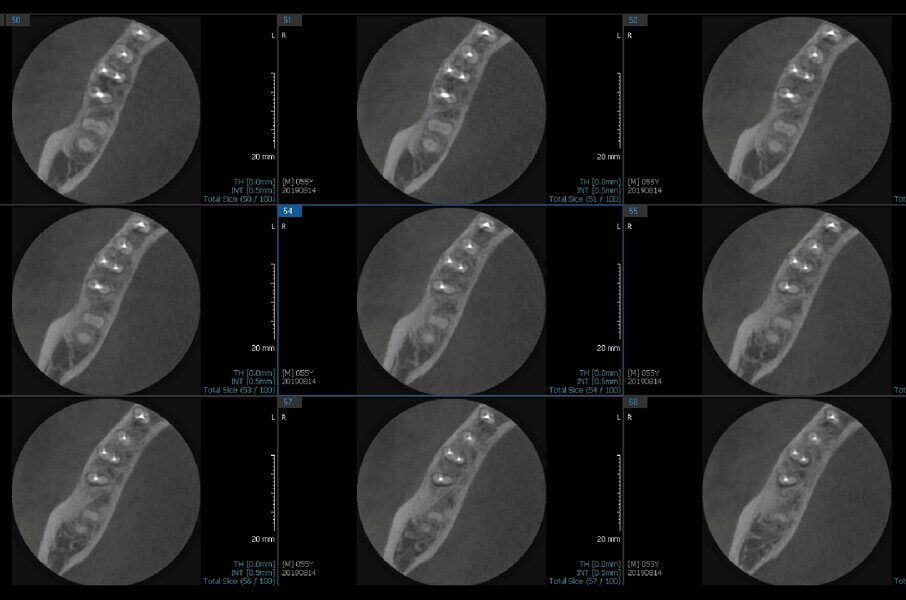

Fig.2a: Pre-op CBCT images of tooth #46: No obturation material in the distal and mesiobuccal canal (a); scanty obturation of the canals and breach of the floor of the pulp chamber, no obturation beyond a few millimetres down the orifice (b & c); radiolucency in the furcation area and periapical region of both roots (d -g).

Fig.2b: Pre-op CBCT images of tooth #46: No obturation material in the distal and mesiobuccal canal (a); scanty obturation of the canals and breach of the floor of the pulp chamber, no obturation beyond a few millimetres down the orifice (b & c); radiolucency in the furcation area and periapical region of both roots (d -g).

Fig.2c: Pre-op CBCT images of tooth #46: No obturation material in the distal and mesiobuccal canal (a); scanty obturation of the canals and breach of the floor of the pulp chamber, no obturation beyond a few millimetres down the orifice (b & c); radiolucency in the furcation area and periapical region of both roots (d -g).

Fig.2d: Pre-op CBCT images of tooth #46: No obturation material in the distal and mesiobuccal canal (a); scanty obturation of the canals and breach of the floor of the pulp chamber, no obturation beyond a few millimetres down the orifice (b & c); radiolucency in the furcation area and periapical region of both roots (d -g).

Fig.2e: Pre-op CBCT images of tooth #46: No obturation material in the distal and mesiobuccal canal (a); scanty obturation of the canals and breach of the floor of the pulp chamber, no obturation beyond a few millimetres down the orifice (b & c); radiolucency in the furcation area and periapical region of both roots (d -g).

Fig.2f: Pre-op CBCT images of tooth #46: No obturation material in the distal and mesiobuccal canal (a); scanty obturation of the canals and breach of the floor of the pulp chamber, no obturation beyond a few millimetres down the orifice (b & c); radiolucency in the furcation area and periapical region of both roots (d -g).

Fig.2g: Pre-op CBCT images of tooth #46: No obturation material in the distal and mesiobuccal canal (a); scanty obturation of the canals and breach of the floor of the pulp chamber, no obturation beyond a few millimetres down the orifice (b & c); radiolucency in the furcation area and periapical region of both roots (d -g).